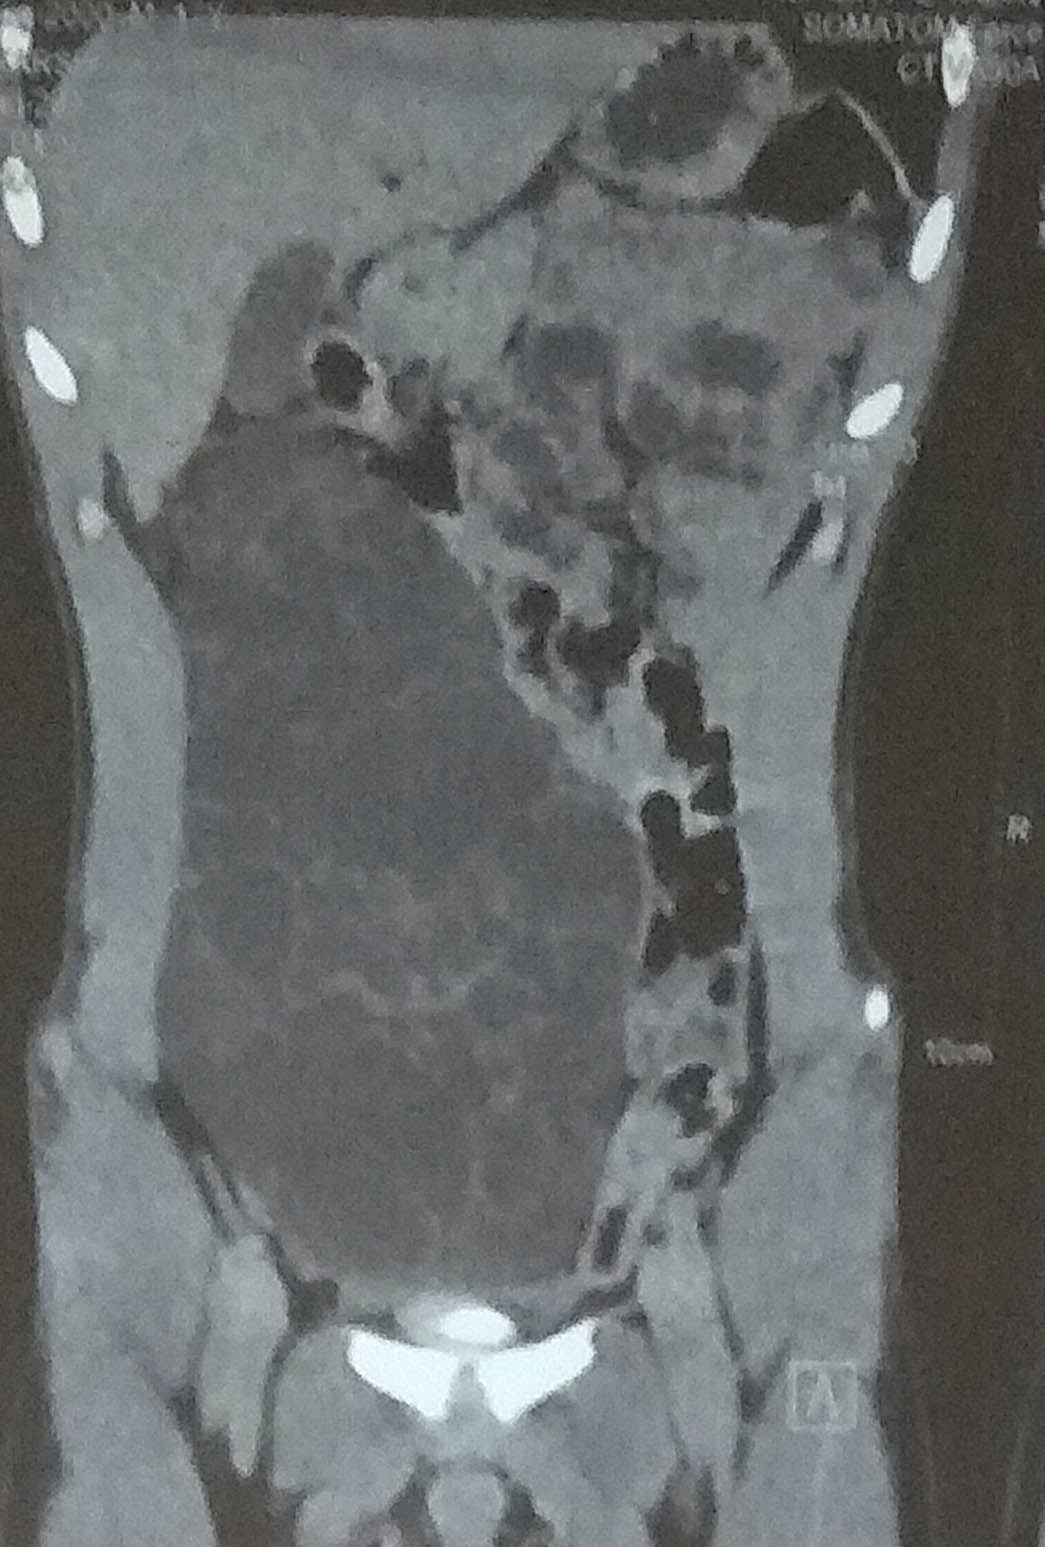

An 18-year-old male presented with complaint of gradually progressive swelling in abdomen since 1 year. His physical parameters and routine haematological investigations were within normal limits. There was no history of past abdominal surgery. CECT revealed a large well-defined multiseptated cystic lesion in the right side of the abdomen extending from the sub-hepatic region to the pelvis, displacing the bowel loops to the left side as well as partially compressing the urinary bladder but with no internal calcifications. The impression given was that of a cystic retroperitoneal neoplasm with internal septations and the differentials suggested were Cystadenoma and Lymphangioma [Table/Fig-1]. The patient underwent surgical excision of the mass. On gross examination, a single, globular, cystic, grey white, soft piece of tissue was received, measuring 20 x 12 x 6 cm. On cutting, 300 ml of clear fluid came out. Cut surface showed multiloculations throughout the specimen. No solid areas were seen [Table/Fig-2]. Multiple sections from various areas were taken and submitted for processing. Histopathological examination showed multiple cystic areas of variable size filled with proteinaceous fluid and lined by a continuous epithelium which was predominanlty cuboidal to low columnar and flat at few foci. Intervening stroma was fibrous with few congested blood vessels and chronic inflammation. No atypia was seen. The histological findings were consistent with a Benign Multicystic Pathology [Table/Fig-3,4 and 5]. IHC for Calretinin and CD 31 was done and calretinin turned out to be positive [Table/Fig-6]. Hence, the diagnosis of Multicystic Mesothelioma was given. The patient has been kept on regular follow-up and was doing fine till the time of writing this paper.

CECT showing a well-defined multiseptated cystic lesion in right side of abdomen with displacement of bowel loops.